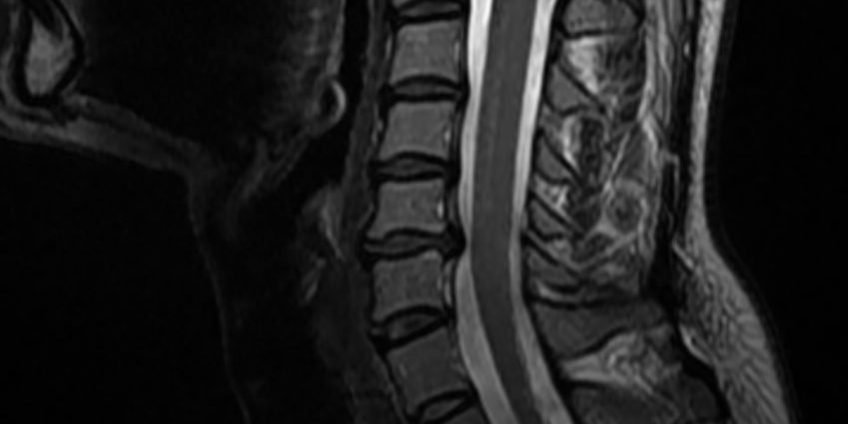

Ο απεικονιστικός έλεγχος έλεγχος με μαγνητική τομογραφία της αυχενικής μοίρας της σπονδυλικής στήλης (ΑΜΣΣ) ανέδειξε κήλη μεσοσπονδύλίου δίσκου στο επίπεδο Α5/6 και ευθειασμό της ΑΜΣΣ.

Διενεργήθη πρόσθια δισκεκτομή Α5/6 και τοποθέτηση τεχνητού δίσκου (Cadisc-C).